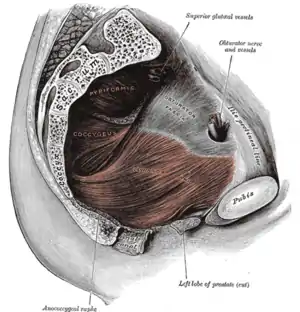

Symphysis pubis exposed by a coronal section. Left levator ani from within.

Left levator ani from within. The obturator externus.